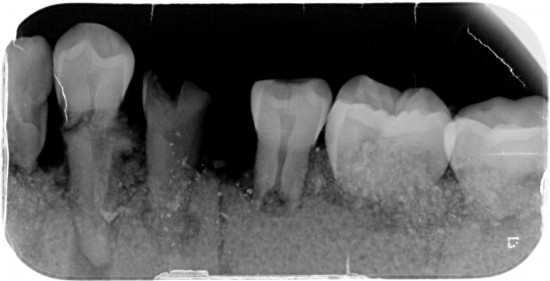

Linker helft 3 molaren ,1 premulaar , 1 gebroken premulaar ,1 hoektand , 3 snijtanden .

Rechter helft 3 molaren , 2 premularen , 1 hoektand, 2 snijtanden .

Totaal 5 snijtanden ?

Dit kaakje werd door mijn tandarts grondig bekeken en róntgen foto,s van gemaakt .

Met zijn  langdurige ervaring  uit zijn eigen praktijk. Kunnen namelijk  Molaren verkeerd om zitten. (zie 1ste  molaar linker kaak)

Tevens kunnen er zowel  tanden teveel of te weinig voorkomen .( zie 5 snijtanden ) . De 5de premulaar en hoektand lijken maar een  tand  te zijn , zie rechterkaak. Rontgenfoto wijst echter uit dat het toch 2 aparte tanden zijn .